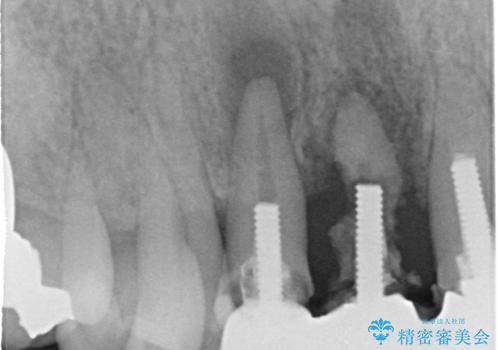

レントゲンを撮影すると保存が難しい歯がありました。

①保存不可の歯の抜歯・根管治療

②矯正治療

③セラミックの装着

という流れで行いました。